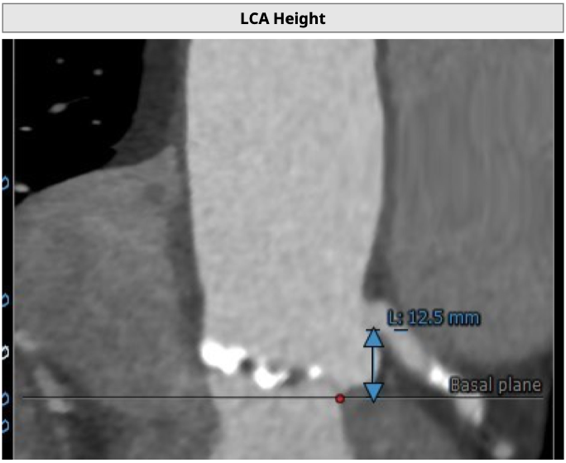

主动脉根部评估

CT 数据显示该患者为Type1型二叶式主动脉瓣

无冠瓣钙化严重,HU850:448mm³

瓣环水平夹角46度